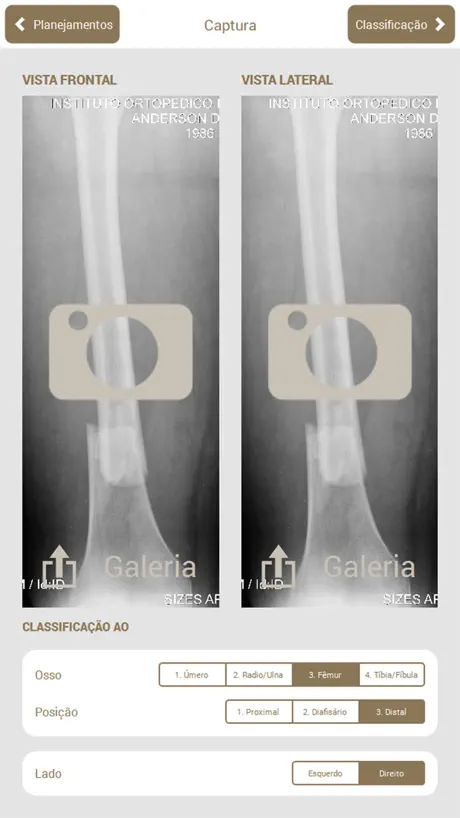

Osteotrauma é um aplicativo que auxilia no planejamento de cirurgias ortopédicas.

O objetivo do planejador é auxiliar o médico em todas as etapas do planejamento de cirurgias ortopédicas em fraturas de ossos longos.

No aplicativo, é possível executar os mesmos passos que são feitos em um planejamento manual: Escolha da radiografia, Classificação AO, Seleção e recorte das partes, Redução, Planejamento dos Implantes, Preenchimento da ficha do paciente, Geração de relatório e Edição manual do relatório gerado (que pode ser exportado em PDF).

O objetivo do planejador é auxiliar o médico em todas as etapas do planejamento de cirurgias ortopédicas em fraturas de ossos longos.

No aplicativo, é possível executar os mesmos passos que são feitos em um planejamento manual: Escolha da radiografia, Classificação AO, Seleção e recorte das partes, Redução, Planejamento dos Implantes, Preenchimento da ficha do paciente, Geração de relatório e Edição manual do relatório gerado (que pode ser exportado em PDF).